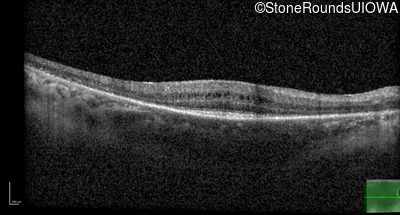

Age at visit: 49 years (Visit 2)